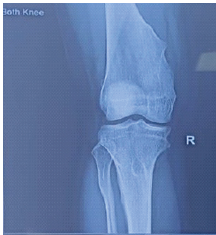

Gouty Arthritis Versus Chondrocalcinosis in a Stiff Knee, A Diagnostic Dilemma – A Case Report

Vineet Thomas Abraham , Muni Srikanth , Kalyan Deepak Sreenivas , Elandevan Gunasekaran , Vignesh Chandrasekar , Aditya Sharma